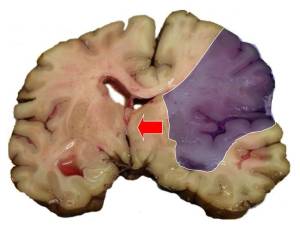

İşemik insult: Bu qan təchizatının çatışmazlığı nəticəsində beynin ocaqlı (fokal) zədələnməsindən əmələ gələn insult növüdür. Bu sindrom 24 saatdan çox çəkən və ya bir sutka ərzində ölümə gətirib çıxaran nevrolojı simptomların kəskin inkişafı ilə xarakterizə olunur. Kəskin serebral işemiya nəticəsində yaranan ocaqlı nevroloji defisit və ya retinal işemiya nəticəsində yaranan görmənin monokulyar pisləşməsi (amaurosis fugax) 24 saat ərzində tam keçib gedirsə, bu sindrom tranzitor işemik həmlə (TİH) kimi təsnifata daxil edilir. Onu demək olar ki, insultların 85%-i işemik insultlardır.

Qanaxma tipli insult: Bu növ beyindəki qan damarından beyinə qan sızdıqda meydana gəlir . Xəstəliyin rast gəlinmə faizi işemik insultdan daha azdır. Ancaq buna baxmayaraq insult nəticəsində ölümlərin 30%-i bu növdən qaynaqlanır.